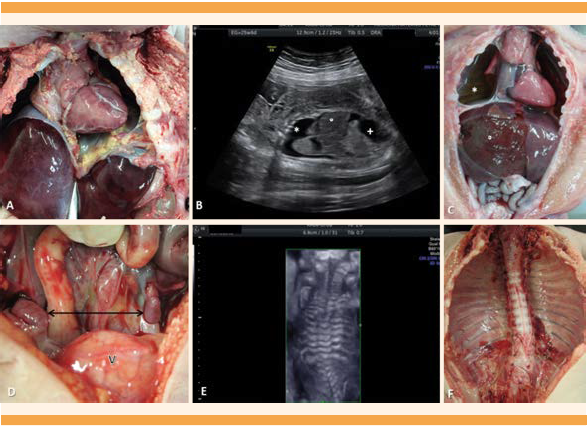

En la letra A se observa hipoplasia pulmonar, caso 3 (37 semanas). En la letra b la imagen de ecografía y la letra C el hallazgo anatomopatológico de hidropesía fetal, observada en el caso 4 con evidencia de derrame pleural bilateral (*), ascitis (+) y hepatomegalia (°). En la letra D se observa criptorquidia del caso 6 (37 semanas), con los testículos en la cavidad abdominal (señalados con flecha) por encima de la vejiga (V). En las letra E y F se muestran la ecografía y el hallazgo anatomopatológico del caso 1, con evidencia de escoliosis dorsolumbar.

Figura 3 Hallazgos anatomopatológicos y ecográficos de los órganos internos.